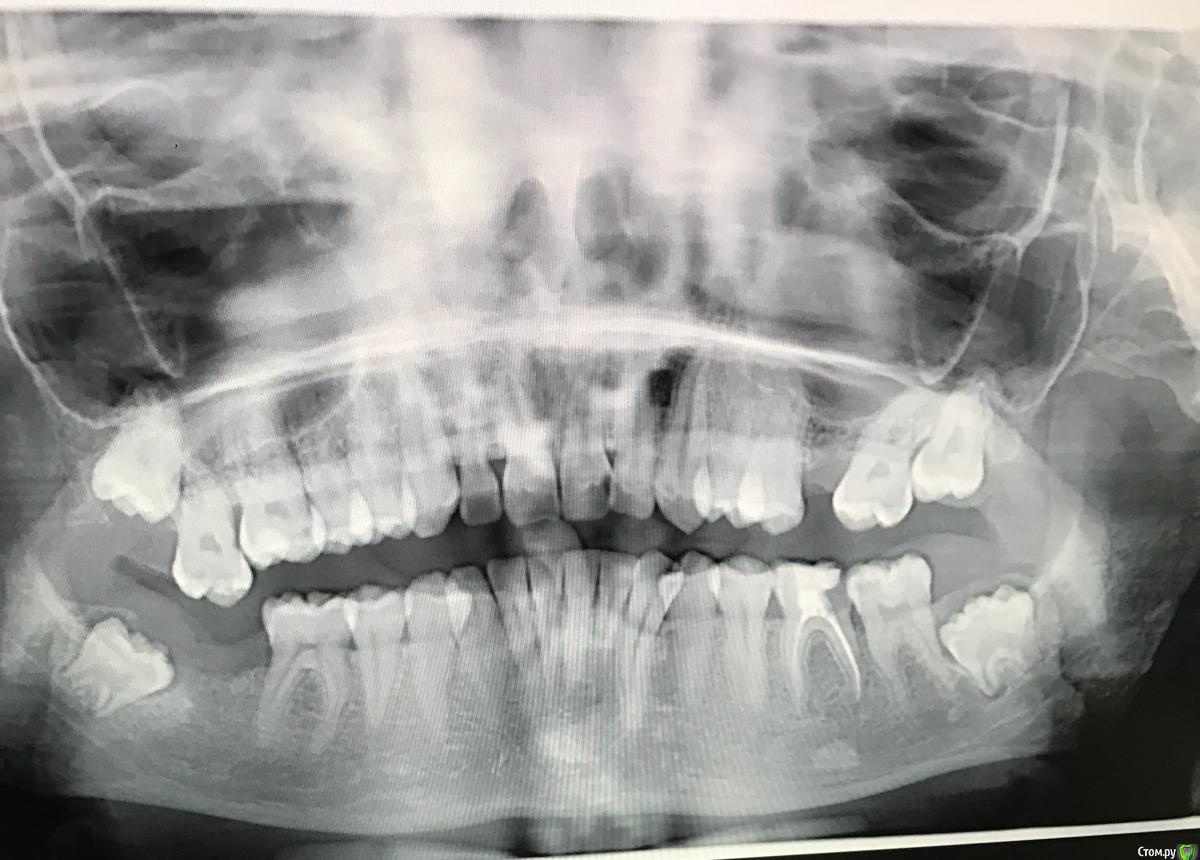

AnnaMatse Опубликовано 28 января, 2018 Поделиться Опубликовано 28 января, 2018 (изменено) Здравствуйте! Кажется , что болит верхняя депульпированная 7ка слева, но это вряд ли, потому что ее пролечили буквально месяца 2 назад. Но снизу есть больная 7ка и депульпированная 6ка( тоже слева, она немного порушилась). Что там у семерки - неизвестно. Стоматолог скажет точно только тогда , когда начнём с ней работать. Но стоматолога моего щас нет. Других боюсь. А, ещё с этой же стороны есть в зачатке 8ка. Ещё проблема в том, что болит десна при нажатии межу 7 и 6 снизу( слева). Так вот. Вопрос в чем. Могут ли нижние зубы иррадировать в верхний пролеченный? И может ли 8ка прорезаться с такими симптомами? Снимок августа. 7 левая уже пролечена, 8 слева уже удалена. Заранее всем спасибо! 7 справа тоже удалена, так как она была пульпитная и хирург сказал , что ее проще удалить, так как она « вышла из кости». Даже на снимке видно , что она ниже других зубов. Изменено 28 января, 2018 пользователем AnnaMatse Ссылка на комментарий

red_butler Опубликовано 29 января, 2018 Поделиться Опубликовано 29 января, 2018 добавилавосьмой удалить, седьмой лечить, шестой убрать пломбу, если пойдет под коронку, то протезировать, если нет, то удалять. Ссылка на комментарий

red_butler Опубликовано 29 января, 2018 Поделиться Опубликовано 29 января, 2018 получается, что 7 болит и отдаёт вверх? Возможно Десна ещё почему -то болит. Между 6 и 7 карман Я уж испугалась , что там что-то серьёзное с ней..7 недельку подождёт? если причина боли в нем, то может и подождет, а может серьезно обостриться а на панораме это уже было видно или только сейчас прояснилось? Я про восьмой. По ОПГ я бы рекомендовал удаление всех мудрых зубов Ссылка на комментарий